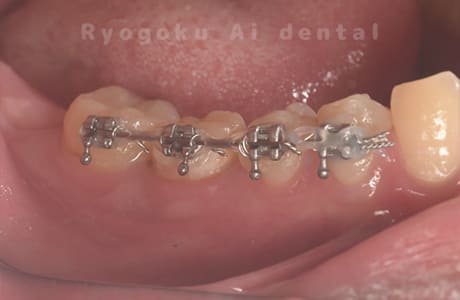

-

歯牙移植咬合面術前 -

移植する親知らず

歯牙移植術直後咬合面

歯牙移植術後咬合面

歯牙移植術前側面

歯牙移植術中側面

歯牙移植術後側面

部分矯正術前咬合面

部分矯正術中咬合面

部分矯正術後咬合面

部分矯正術前側面

部分矯正術中側面

部分矯正術後側面

- 原因

- 重度カリエス

- 治療内容

- 自家歯牙移植、部分矯正

- 治療費用

- 220,000円(移植費用)

110,000円(部分矯正費用)

虫歯が大きく、保存不可能となった歯を上の親知らずと交換する自家歯牙移植を行いました。移植歯が小ぶりであったため、部分矯正を行い問題なく噛み合い、経過良好です。